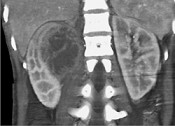

- 单项选择题一女性患者,一月前出现尿频、尿急等症状为引起注意, 现有高热,阅图后最可能的诊断为 ( )

A、急性肾盂肾炎

B、肾脓肿

C、多囊肾

D、肾结核

E、肾癌